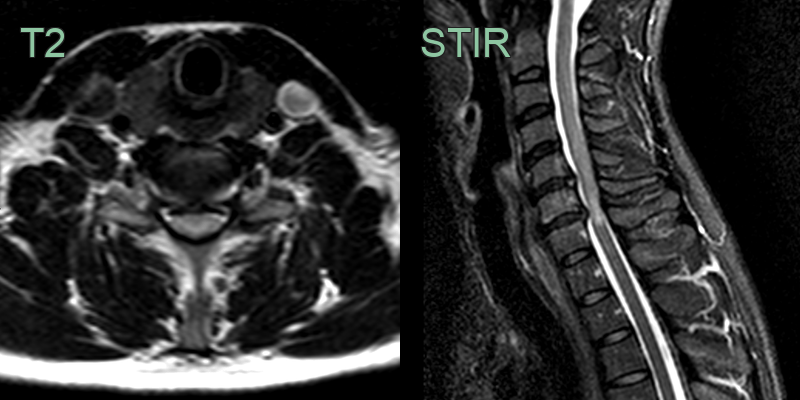

- Magnetic Resonance Imaging (MRI):

- Gold standard for diagnosis

- T2-weighted images: hyperintense signal within the cord

- T1-weighted images: assess for cord atrophy

- Diffusion Tensor Imaging (DTI): assess white matter tract integrity

- Computed Tomography (CT):

- Useful for assessing bony abnormalities

- CT myelography: alternative when MRI is contraindicated